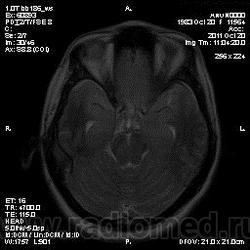

Эта же пациентка... Июль 2011 года....

В анамнезе есть зацепки на энцефалит?Мне ни разу не встречался, поэтому умничать не буду.

А здесь вариант Арнольда-Киари+ платибазия к тому же (?)

мне кажется больше похоже на диффузную глиальную опухоль. Для герпетического нехарактерна локализация и характер контрастирования. Хотя конечно нет правил без исключений..

Евгений Второй, а медиобазальные отделы височных долей - по-моему излюбленная локализация герпетических энцефалитов... Да мне кажется, что серое и белое вещество в равной степени вовлечено в процесс...

Арнольда-Киари можно указать, но вы же понимаете, что он меркнет на фоне основной патологии....

а медиобазальные отделы височных долей - по-моему излюбленная локализация герпетических энцефалитов..

Абсолютно согласен, просто у меня не все картинки раньше загрузились и показалось, что все изменения в лобных долях и базальных ядрах. Снимаю свои возражения.